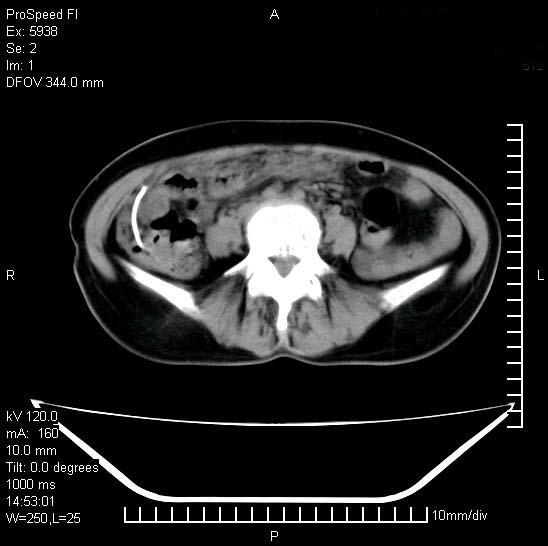

反复小腹疼痛,盆腔积液3年,无发热,曾抗痨一段时间。

右下腹肠管壁增厚,边缘有侵润改变及点状低密度影,内侧可见局限性肿块。考虑-----淋巴瘤或增生型肠结核----盆腔积液-----建议肠镜检查

考虑盆腔及右下腹感染性病变(结核可能)。

结核性腹膜炎伴积液。右侧髂骨骨窗看看,是否有骨质破坏。

提示结核性腹膜炎合并盆腔积液。建议查ppd或tb抗体。

考虑右下腹及盆腔感染性病变(结核?)。